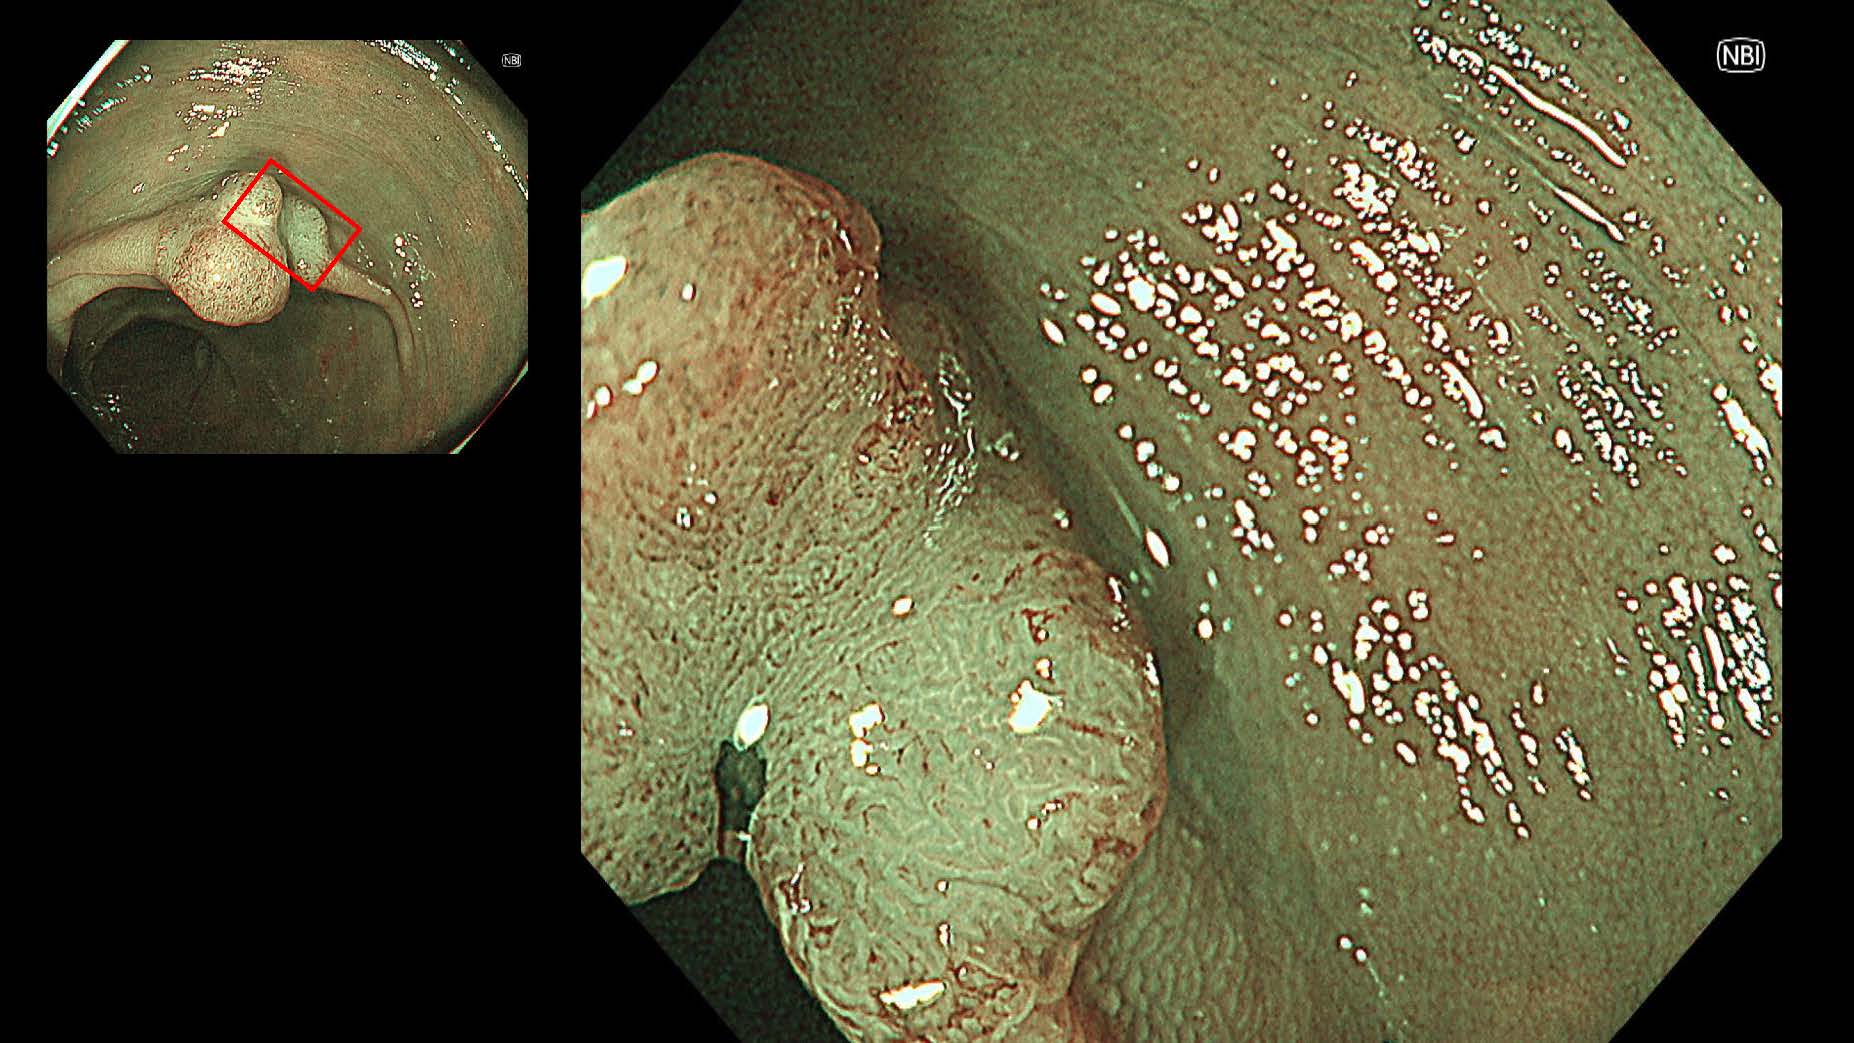

消化管Mapping~大腸~ 2025.6.11

消化管Mapping

消化管Mapping~大腸~

消化器内科

内視鏡検査・治療